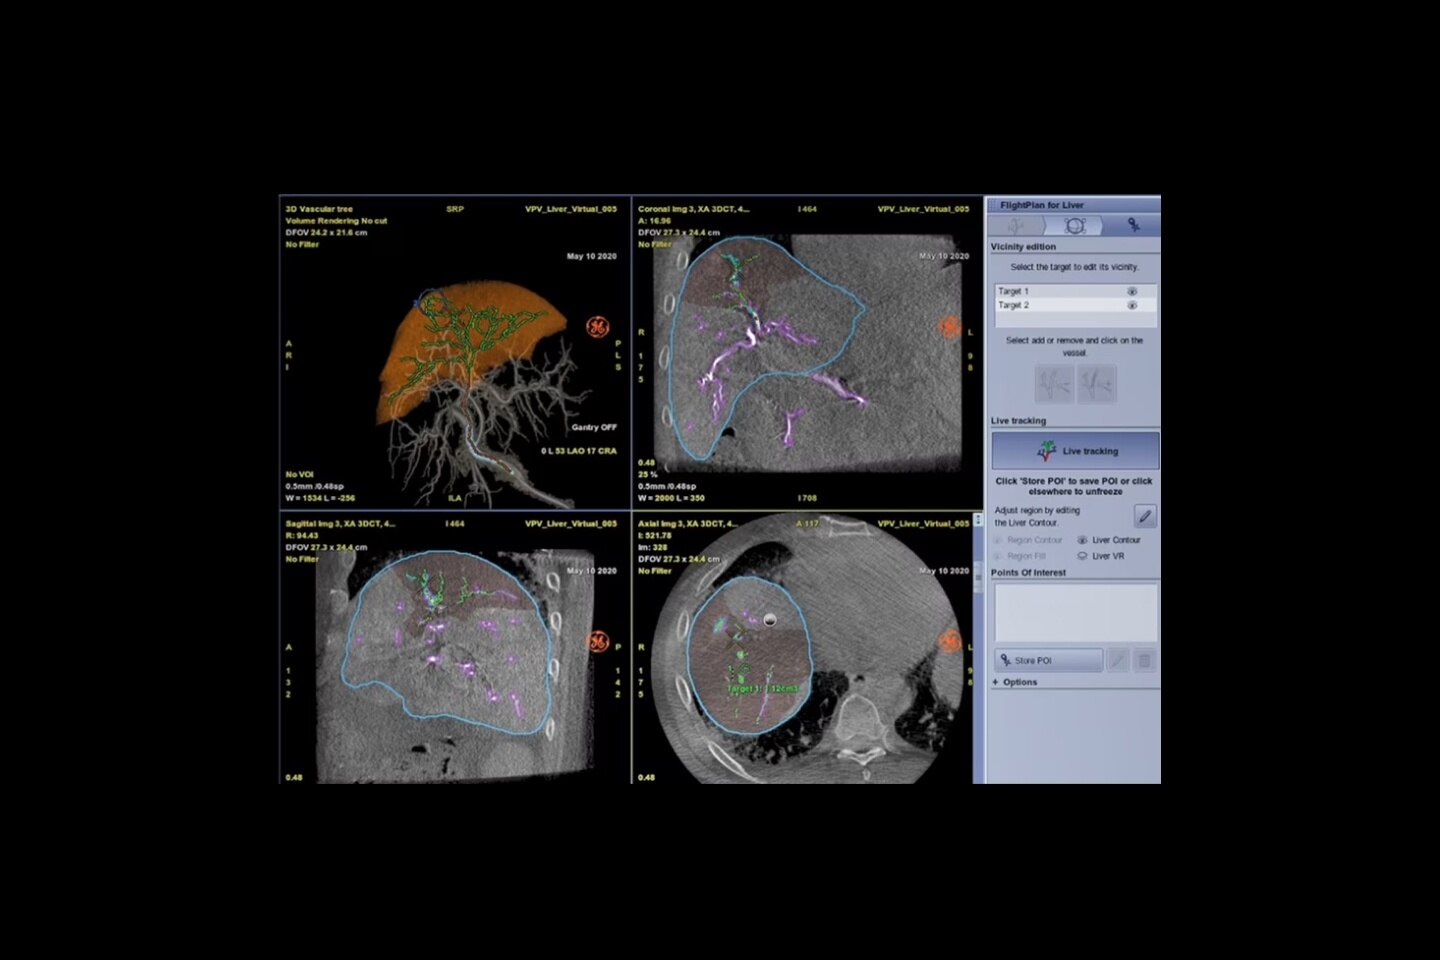

Liver assessment package

With UGAP and 2D SWE staging, hepatic assistant workflow and CEUS FLL analysis

Robust advanced quantification tools: 2D Shear Wave Elastography, UGAP, CEUS, and Fusion Imaging enhance precision and speed.